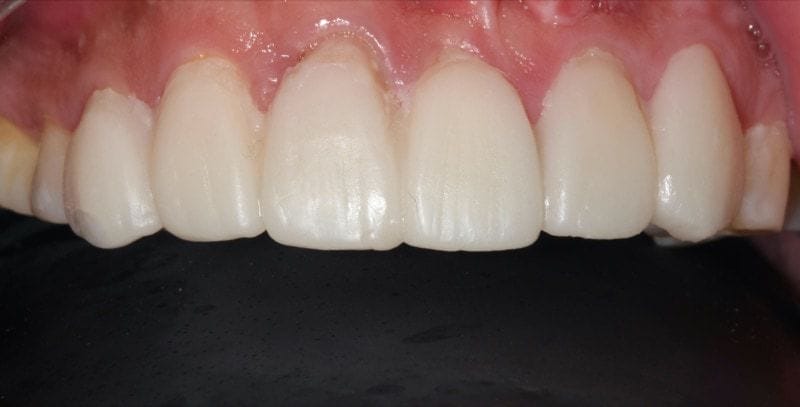

圖示:陶瓷貼片完成後的上排前牙近照,通過數位化流程提高效率和品質

利用陶瓷貼片修復蛀牙或牙齒缺損、改變形態,Mr.Su對美觀改善的成果非常滿意。

把口內掃描技術整合至臨床流程,除了精準度高,感受也會比較舒適。患者不必忍受令人噁心想吐的傳統印模材,數位化設計與製作更可省去寄件往返的時間,效率與品質都大幅增加。依患者的狀況及需求安排下,甚至能夠做到『一日美齒』- 從口腔掃描、陶瓷貼片/全瓷冠製作、配戴全在一天之內完成。